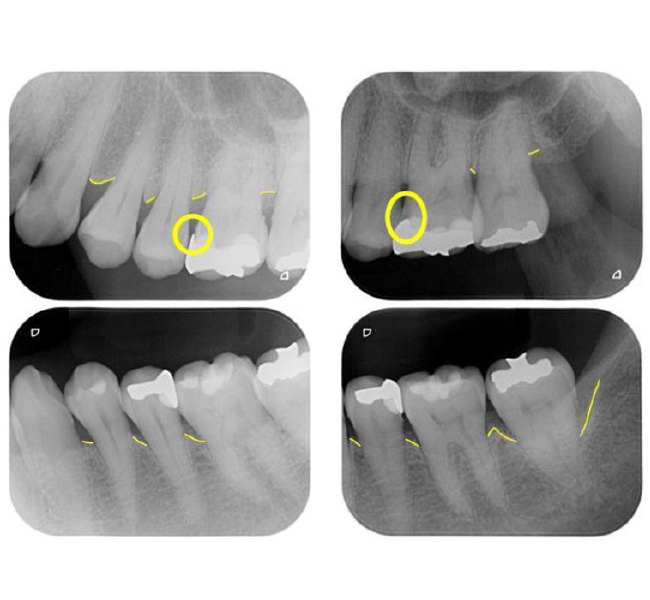

治療前

| 主訴 | 左奥歯が仕事が忙しくなると上下とも痛くなる。 毎月メインテナンスしていた歯科医院が閉院した。 歯周病含め今の状態が気になる。 全体のメインテナンスもしたい。矯正治療はやりたくない。 |

| 治療内容 | 全顎治療:歯周病治療、根管治療、 歯肉弁剥離掻爬術(フラップ手術)、 セラミック治療、ダイレクトボンディング |